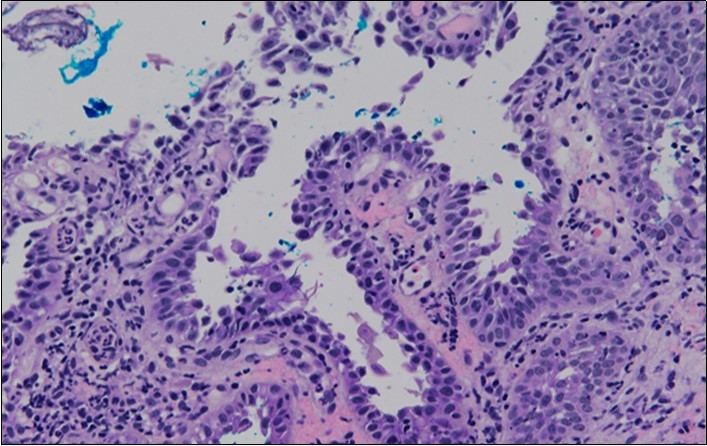

She was discussed at the hospital cyto-pathology conference to clarify the diagnosis. The original cytological smear specimen was reviewed, with features of bi-nucleation and koilocytosis consistent with LSIL. The cervical biopsy was also reviewed, confirming typical features suggestive of cervical pemphigus. (Figure 4a, Figure 4b, Figure 4c)

Figure 4c.Well vascularised dermal papillae with residual basal layer giving rise to tombstone appearance

Well vascularised dermal papillae with residual basal layer giving rise to tombstone appearance